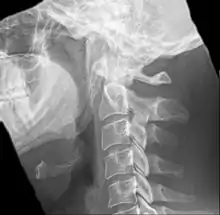

التخيل مهم ويساعد في التشخيص، لذلك يتم تصوير البروز الإبري عن طريق الأشعة المقطعية مع إعادة البناء ثلاثية الأبعاد لأنها التقنية المُثلى في هذا المجال.[2]

البروز الإبري المتضخم يُمكن أن يُري عن طريق صورة بالأشعة السينية لنسيج رخو من الرقبة.